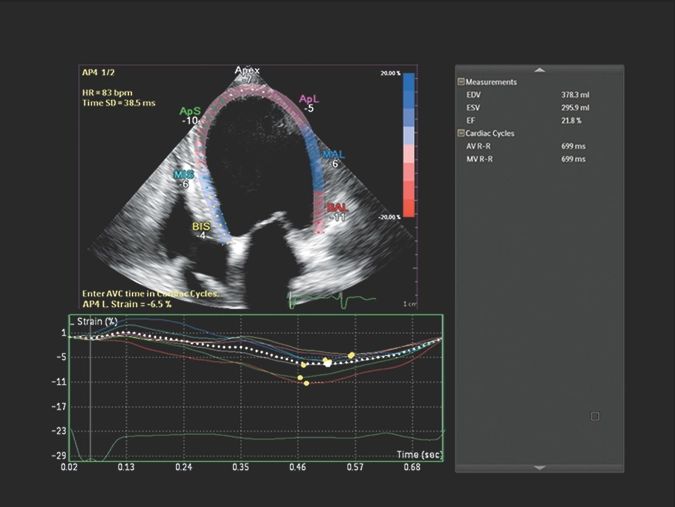

- Кардиология

Функции для кардио-исследований

- Stress Protokol - стресс эхокардиография

- GI 3DQ - количественный анализ 3D

- TDI - тканевый допплер

- Strain Q - функция для оценки скорости движения стенок миокарда

- A2DQ - автоматическое распознавание границ камер сердца и расчет площади, объема левого желудочка и параметров систолы и диастолы левого желудочка, расчет фракционной площади, фракции выброса, максимальной скорости выброса, максимальной скорости быстрого наполнения и фракции предсердного наполнения

- aCMQ - Анализ параметров общей и конкретной сократимости камер сердца

- MVI - функция для точной визуализации микрососудов при помощи картирования прохождения контраста по сосудам

- Contrast Card - функция для отображения микропузырьков в миокарде при введении контраста для анализа микроциркуляции в ЛЖ

- A2DQ - автоматическое распознавание границ камер сердца и расчет площади, объема левого желудочка и параметров систолы и диастолы левого желудочка, расчет фракционной площади, фракции выброса, максимальной скорости выброса, максимальной скорости быстрого наполнения и фракции предсердного наполнения

- CMQ Stress - стресс эхокардиография для оценки глобальной и регионарной сердечной функции в различных состояниях